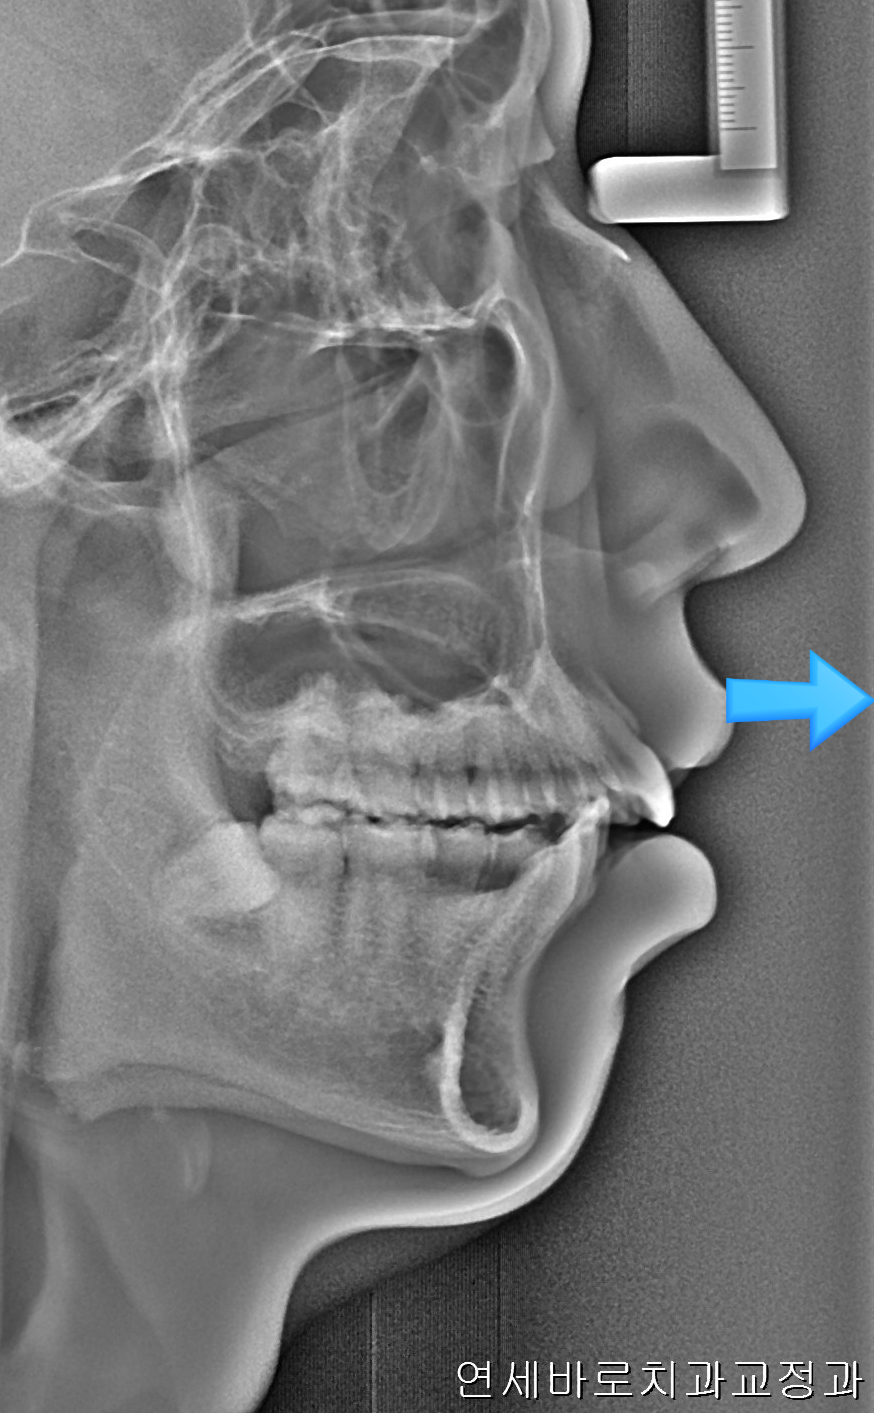

앞니가 많이 돌출되어 있는 환자분이었습니다.

어금니와 송곳니 관계를 보면 발치를 하는 것이 치료를 하는 입장에서 훨씬 편할 수 있는 상태였습니다.

환자분은 심한 무턱과 단안모의 형태를 가진 안모의 소유자였습니다.

이런 분들은 자칫 입이 과하게 들어가면 안모가 많이 안좋아질 수 있죠.

환자분과 상담 후 비발치로 최대한 입을 넣기로 했습니다.